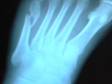

Здравствуйте, 11.04.2014 сломала 5 плюсневую кость на левой стопе со смещением, обратившись в приемное отделение своего города, меня госпитализировали для дальнейшего оперативного вмешательства. Положили лангет и операцию назначили на 15.04.2014. После проведения обследования, у меня в анализах показало низкий уровень лейкоцитов и тромбоцитов (23). Анастазиолог разрешение на операцию не дал. Лечащий травмотолог сказал, что впринципе операцию можно и не делать. Так срастется. А на мой вопрос: Что дальше? Будет ли беспокоить меня нога? Буду ли я кульгать? Будет ли кривая нога? Доктор мне ничего не ответил. И меня выписали на амбулаторное лечение.

Скажите правильноли наши доктора поступили? Есть ли какие либо препараты для поднятия тромбоцитов во время операции? Может можно было вправить мой перелом без вмешательства (под наркозом)? Может пока не поздно можно обратится в клинику в Минске, т.к. у нас лежишь в больнице и никому до тебя дела нет.